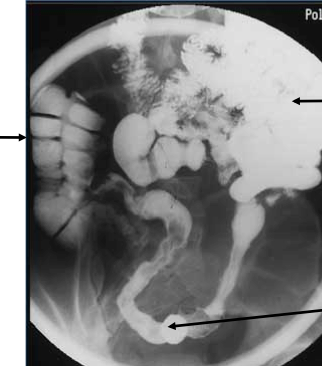

What is going on here? Arrows?

What do you see here?

What is going on here?